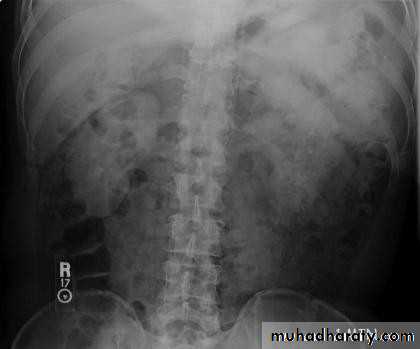

• Intravenous (Excretory) Urography

• Immediate• Compression

• 5 minutes

• Check the Kidneys: outline, size, site

• Check the calyces: cupped• Check renal pelvis and ureter

• Check the bladder